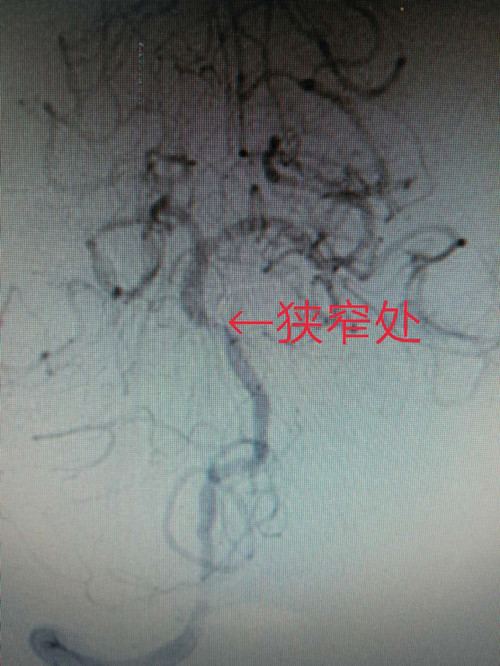

病例简介:患者男性,65岁,2月前发生脑干梗塞,经药物治疗后好转,未留后遗症。此次因一侧肢体无力来我院治疗,核磁显示脑干急性梗死,MRA示基底动脉中段重度狭窄,全脑血管造影显示基底动脉中段狭窄,狭窄率90%。向家属交代病情后,同意介入手术治疗。